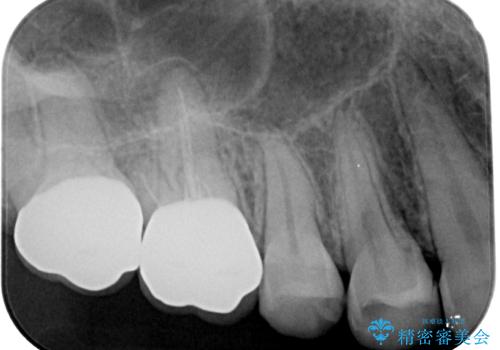

スペースが整った段階で、右下の第一大臼歯と第二大臼歯にインプラントを埋入。

その後、挺出していた右上第一大臼歯と第二大臼歯に装着されていた銀歯についても、審美性と適合性の向上を目的に、オールセラミッククラウンにやり替えました。

これにより、より自然で美しい見た目と、高い精度の咬合が得られています。